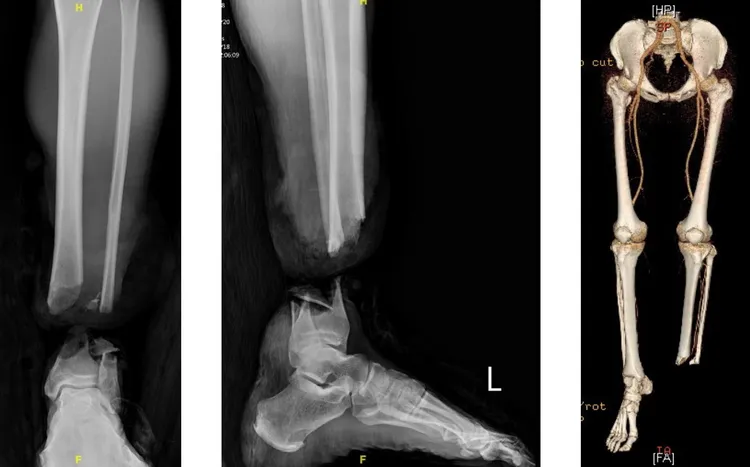

吳先生的左小腿被漁船螺旋槳截斷。長庚醫院提供

基隆長庚整形外科醫師藍靖宇指出,當天的緊急手術先由骨科陳建豪醫師完美的將骨頭復位採取外固定後,再由整形外科醫師接手迅速進行顯微重建手術,這需要高度的技術和精準性,因為不僅要將患者的小腿成功植回,還要確保成功植回後能恢復日常生活,甚至繼續從事潛水活動的功能性。

藍靖宇先從吳先生正常的右小腿取下25至30公分的靜脈血管做移植,再重建斷肢左小腿的前及後側的兩套血循系統,同時也重新吻合主要的運動及感覺神經,並修復了小腿包含前側、後側、外側幾乎所有的肌肉與肌腱。